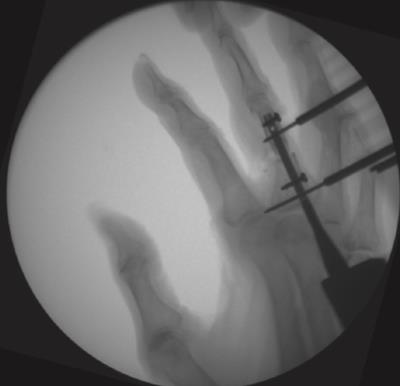

Locking Hand Nail System

• The Locking Hand Nail System from Skeletal Dynamics is an intramedullary fixation system designed for the stabilization of fractures of the metacarpals and proximal phalanges

• The device provides minimally invasive internal fixation through a headless, cannulated nail that is inserted within the medullary canal to maintain fracture alignment while minimizing soft-tissue disruption

• The system incorporates distal locking screw options to enhance rotational and axial stability, allowing controlled fixation of extra-articular fracture patterns

• The Locking Hand Nail System is part of a specialized hand fracture fixation platform and includes multiple nail diameters and lengths, dedicated instrumentation, and compatible locking screws to accommodate variations in hand anatomy and fracture configuration